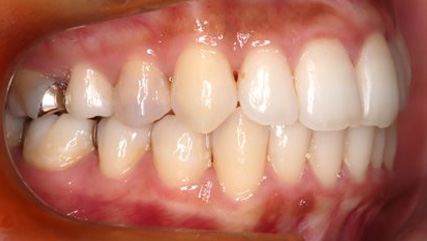

治療前

治療終了前